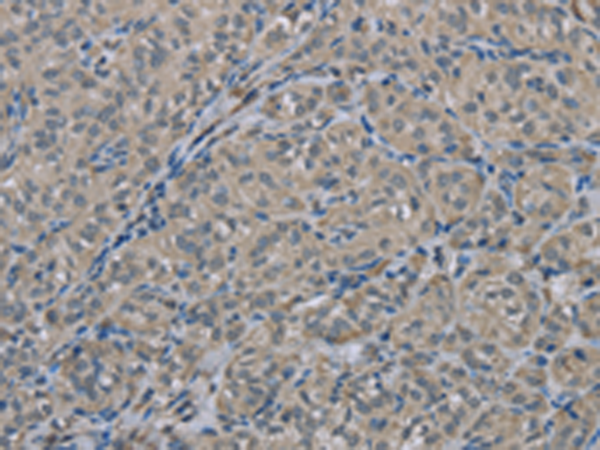

分类: 科研抗体货号: P08315别名: MLC-B; MRLC2应用: WB,IHC反应种属: Human, Mouse, Rat